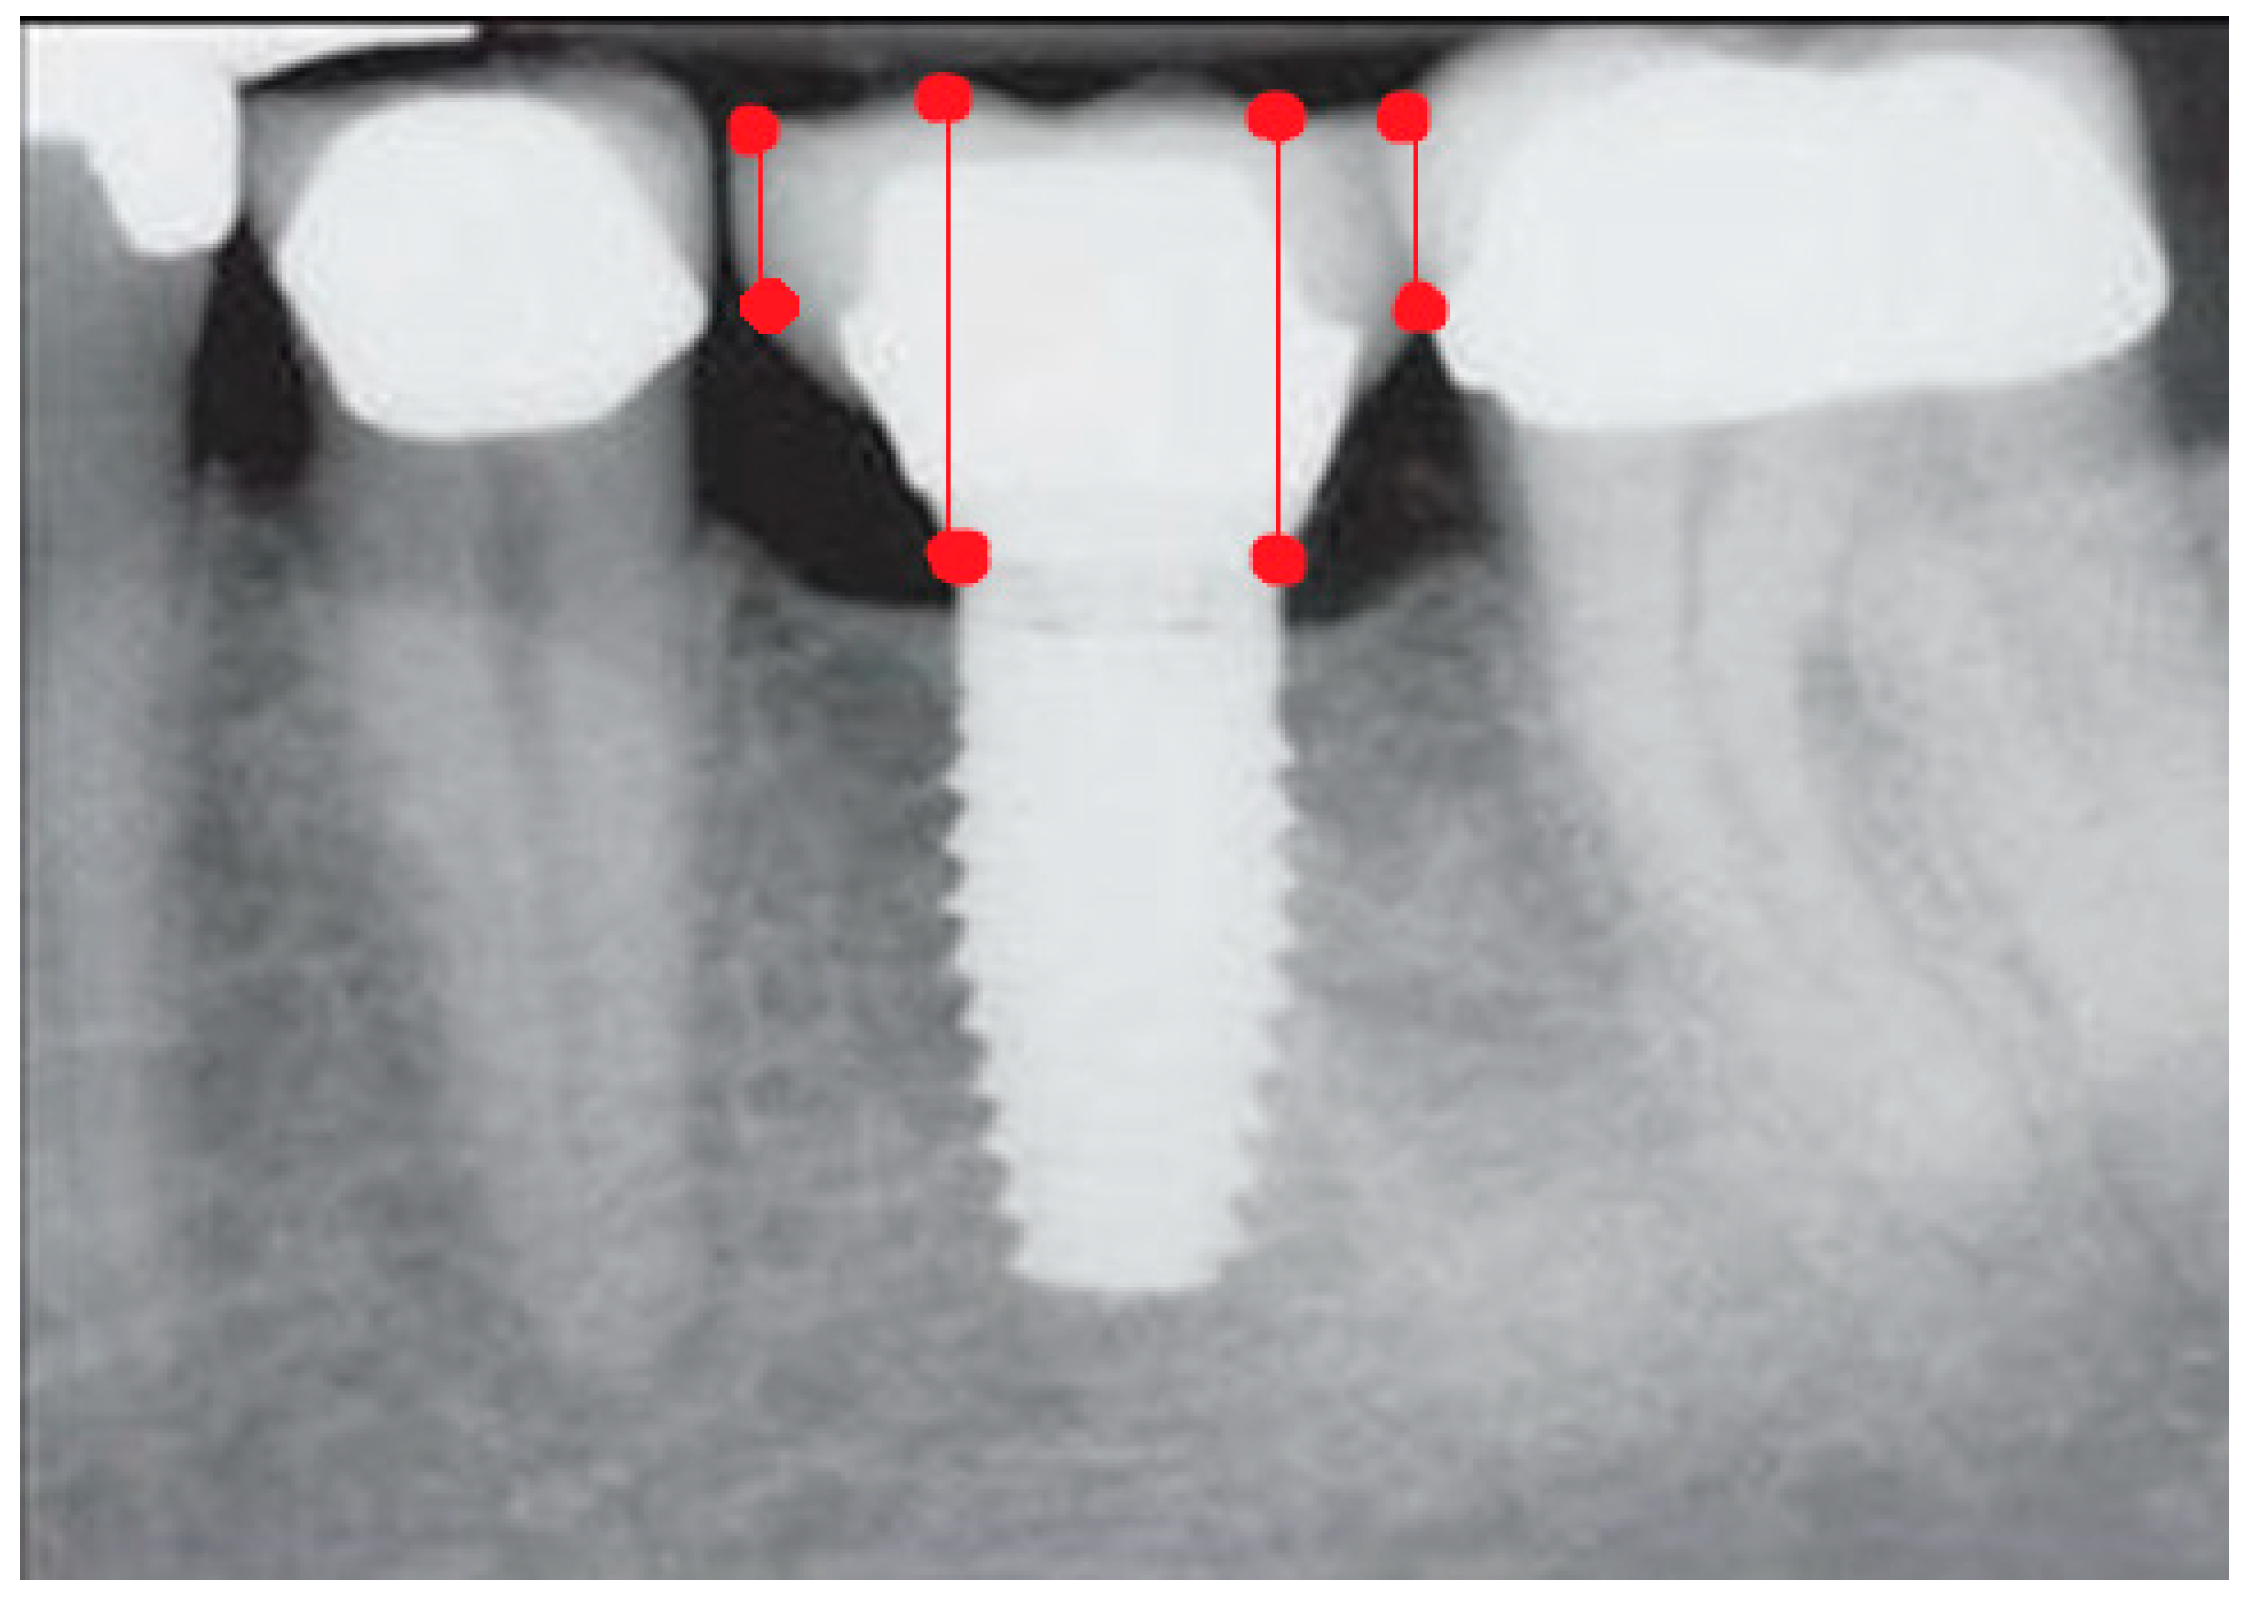

- Measurement of mesial and distal bone loss: Clinically, an increase in the probing depth of the peri-implant pockets, both mesial and distal, was recorded using a calibrated probe with a force of 0.25 N. Radiographically, mesial and distal peri-implant bone height loss was measured using properly performed radiological projections. In fewer than five patients, statistically significant findings in cases of bone loss were difficult to achieve.